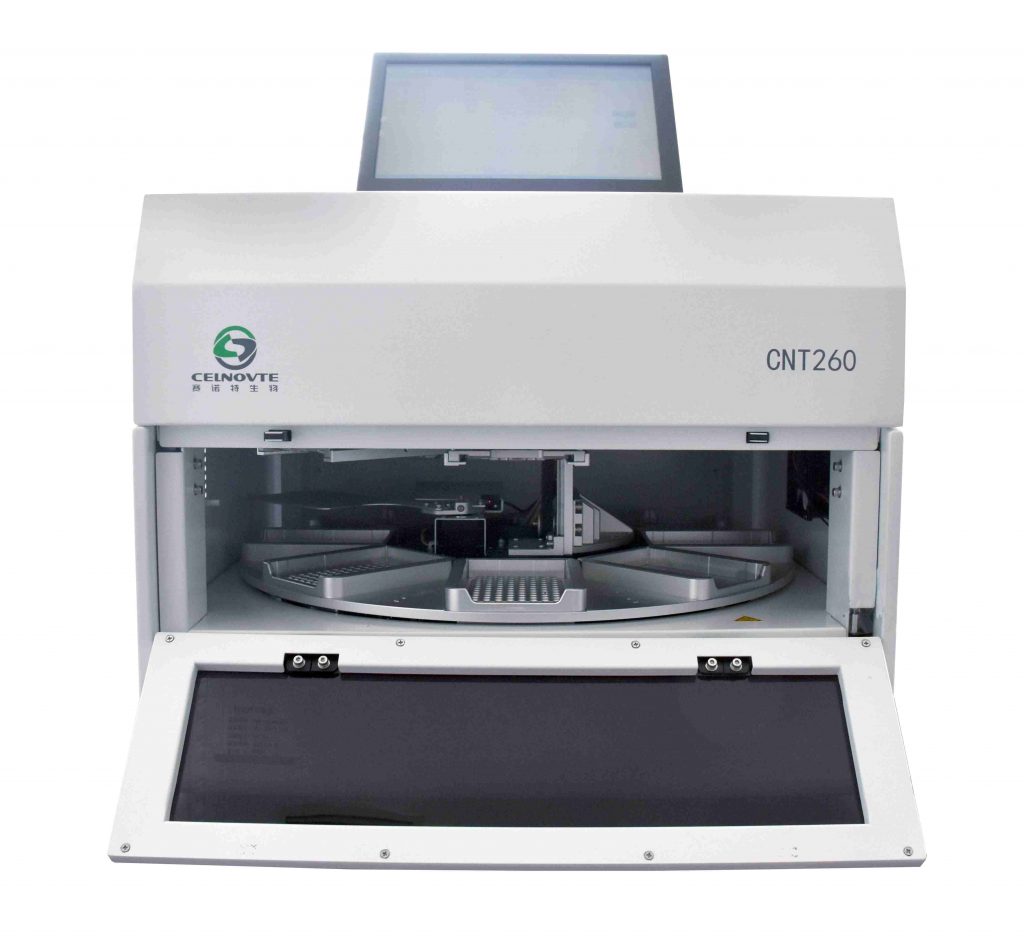

The quality of any molecular test relies fully on the purity of the starting sample. The Celnovte Nucleic Acid Extractor is an automated option built to provide high amounts of pure DNA and RNA from different sample types. By handling this vital first step automatically, it cuts down on human mistakes. It also ensures the steady quality needed for dependable later uses like ISH and sequencing.

Automation and Consistency with Advanced Instrumentation

The ISH process is complex and includes many exact steps. The Celnovte ISH Processor handles this whole workflow automatically, from removing paraffin to hybridization and signal spotting. This not only saves technician time but also greatly boosts repeatability and standard levels across samples. Such consistency is vital for clinical correctness.

Celnovte offers more than single items; we provide a full answer. Our range includes all the needed Consumables, reagents, and detection systems. All are tuned to work together without issues. By picking Celnovte, your lab gets a checked, start-to-finish workflow for advanced molecular diagnostics.

A: Celnovte provides a comprehensive suite of solutions for molecular pathology, including automated Nucleic Acid Extractors, ISH Processors, and a portfolio of ISH probes like CISH, FISH, and our high-sensitivity SUPER-ISH™. We also supply all the necessary Consumables for a complete workflow.